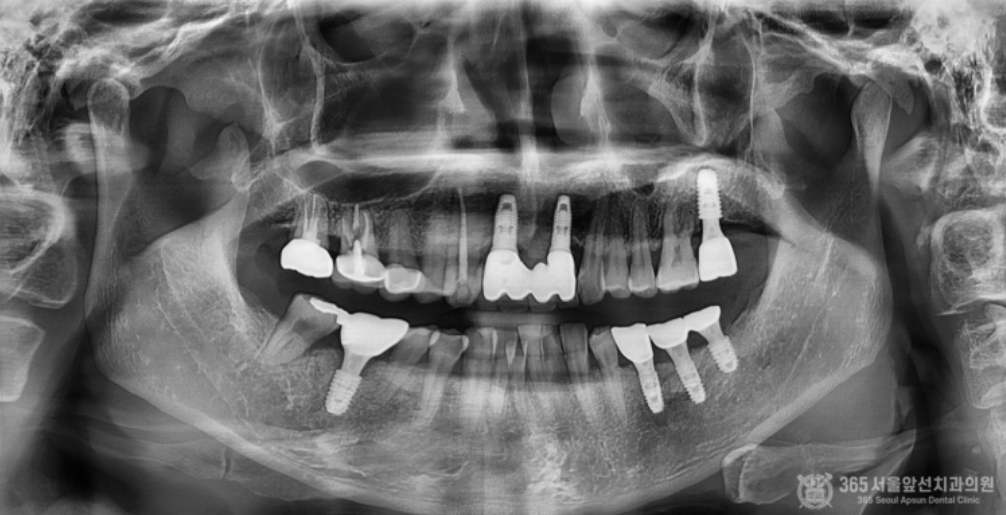

촬영일시 : 2024.06.10 왼쪽 위아래 안좋은 치아들을 발치하고 수직골증대술과 상악동측방거상술을 동시에 진행하여 수술을 했습니다. 상당히 많은 골이식이 들어갔고 부족한 잇몸을 늘려주는 술식까지 동시에 진행되었기때문에 난이도가 높은 수술이라고 보시면 되겠습니다.